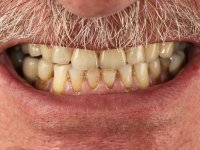

Frequent fracturing of composite resin restorations, in central upper incisives. Patient was also displeased with the “aged” look of his teeth.

Male patient, 64 years old, non-smoker. Presented widespread dental wear. Both superior and inferior central incisives were lacking enamel on incisal edges, with exposed dentin. Superior central incisives had been previously restored with composite resin, which offered tolerable aesthetics and was prone to frequent fracturing.